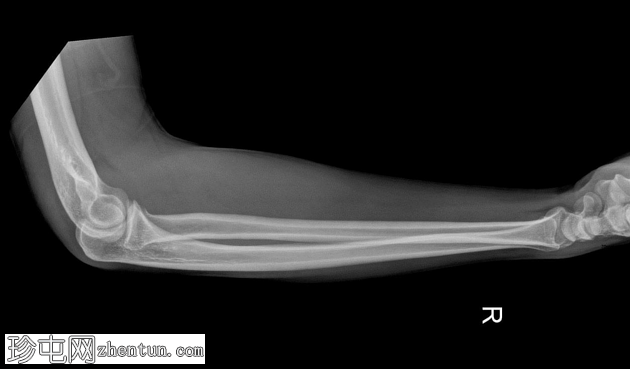

侧位片

3.png

桡骨头关节内粉碎性骨折,关节面轻微凹陷。肱骨远端前侧可见移位的骨碎片,桡骨头位片上清晰可见。可见前后脂肪垫征,提示肘关节积液。

未见肘关节脱位,肱桡骨小头排列保持正常。冠突水平可见复合阴影,可能与软组织重叠或投影伪影有关。桡骨和尺骨骨干外观完整,无骨折征。周围软组织肿胀。

本例患者前后脂肪垫征均存在,证实存在关节内积液,符合急性关节内损伤的诊断。未见肘关节脱位或相关骨干骨折,提示损伤仅限于桡骨头。

根据影像学特征,该骨折符合 Mason III 型损伤,涉及多个骨折碎片和关节面破坏。此类骨折需要骨科评估,并根据其稳定性和移位情况,选择手术治疗或桡骨头置换术。